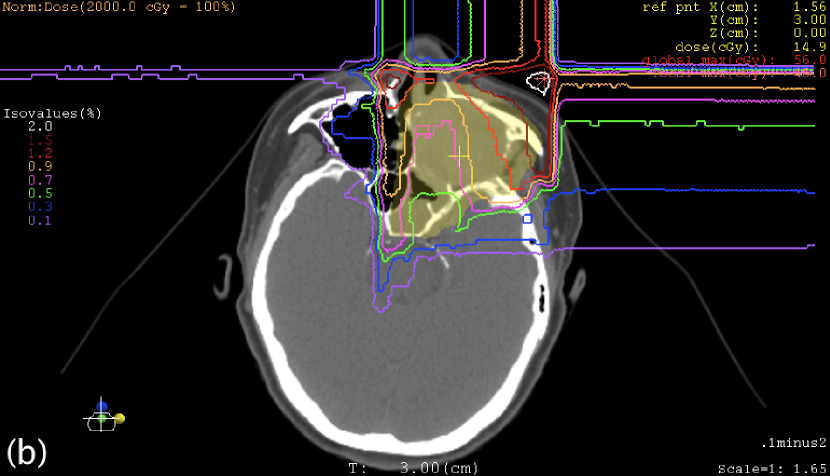

III.3 Case study

Table 3 shows the maximum WE thicknesses of the range compensators. Except for the posterior beam in the sacrum case, range compensation was large as it had been expected for oblique-incident beams. Figures 4 and 5 show the plan dose distributions, in which the reduction of clinical dose was 0.30% at the isocenter in the sacrum case, 0.75% at the isocenter in the nose-and-sinus case, and mostly within 1% in these targets. In the nose-and-sinus case, the dose reduction greater than 2% occurred only in the air that happened to be included in the dose-calculation volume. Relatively speaking, the dose reduction was greater in the posterior part of the sacrum target and in the anterior-left (away from nose) part of the nose-and-sinus target, which was caused by locally shallower target depth and hence larger range compensation in the fields.